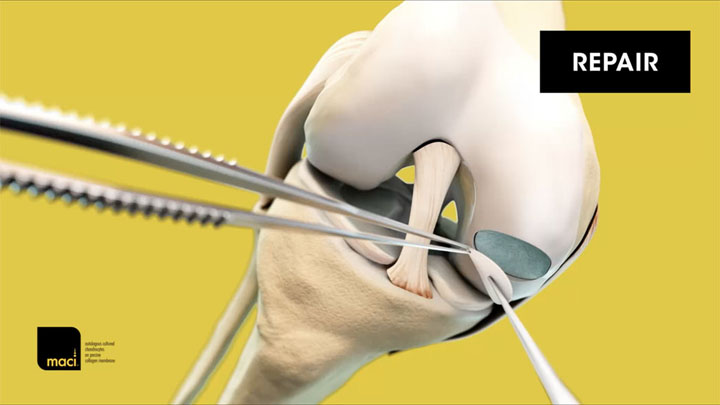

MACI® (autologous cultured chondrocytes on porcine collagen membrane) is an autologous cellularized scaffold product that is indicated for the repair of single or multiple symptomatic, full-thickness cartilage defects of the adult knee, with or without bone involvement.

MACI is intended for autologous use and must only be administered to the patient for whom it was manufactured. The implantation of MACI is to be performed via an arthrotomy to the knee joint under sterile conditions.

The amount of MACI administered is dependent upon the size (surface in cm2) of the cartilage defect. The implantation membrane is trimmed by the treating surgeon to the size and shape of the defect, to ensure the damaged area is completely covered, and implanted cell-side down.